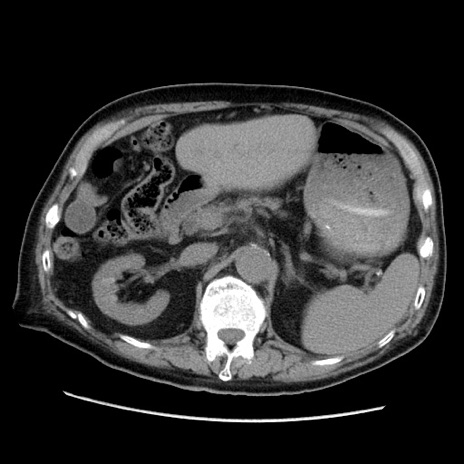

症例21(横断像)

【症例】70歳代男性

【現病歴】肝硬変・肝細胞癌にてかかりつけの方。約9時間前に食後より腹痛出現。症状が徐々に増悪し、嘔吐出現したため来院。

【既往歴】肝硬変、肝細胞癌(RFA、TACE後)